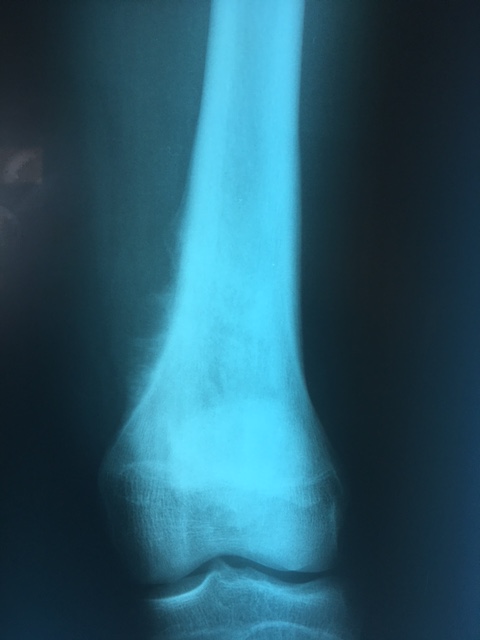

Հիվանդ Ն., 1998 թ.ծ., ընդունվել է ՈւԱԿ 2016թ. հուլիսին, որտեղ ախտորոշվել է` աջ ազդրոսկրի դիստալ հատվածի օստեոգեն սարկոմա: Հիվանդը ստացել է 4 կուրս նախավիրահատական քիմիաթերապիա, որից հետո վիրահատվել է: Կատարվել է` ազդրոսկրի դիստալ հատվածի և ծնկան հոդի սեգմենտար մասնահատում մեգաէնդոպրոթեզավորումով:

Վիրահատությունն իրականացրել են Ոսկրային պաթոլոգիայի բաժանմունքի վարիչ Սերգեյ Սեինյանը, օրթոպեդ-ուռուցքաբաններ Ալեքսանդր Սեինյանը և Էդգար Նիկողոսյանը:

Հետվիրահատական շրջանում հիվանդը կրկին ստացել է 4 կուրս քիմիաթերապիա:

Վերջույթի ֆունկցիան պահպանված է։